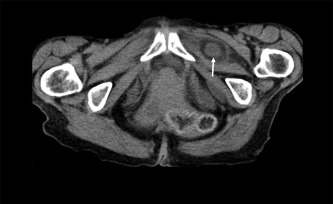

Abdominal X-ray examination showed dilatation of small bowel loops in entire abdomen. CT scan demonstrated dilated bowel loops (Figure 1) and incarcerated bowel between the external obturator and pectineal muscles (Figure 2), suggestive of bowel obstruction secondary to incarcerated obturator hernia. Four of the obturator hernias were in the left and the other two in the right.

Dilated small bowel loops in the lower abdomen and pelvis.

Figure 1.